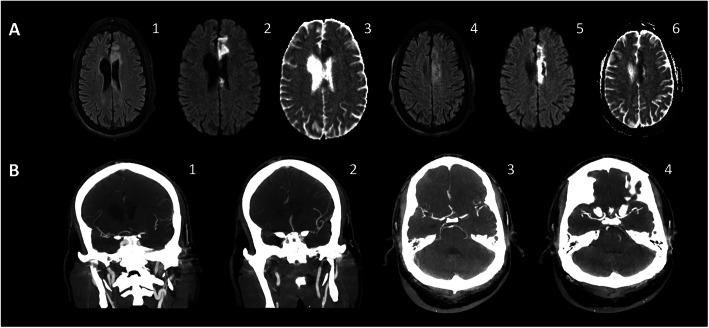

Coronavirus disease 2019 (COVID-19) is a highly infectious pandemic caused by a novel coronavirus called severe acute respiratory syndrome coronavirus 2 (SARS-CoV-2). It frequently presents with unremitting fever, hypoxemic respiratory failure, and systemic complications (e.g., gastrointestinal, renal, cardiac, and hepatic involvement), encephalopathy, and thrombotic events. The respiratory symptoms are similar to those accompanying other genetically related beta-coronaviruses (CoVs) such as severe acute respiratory syndrome CoV (SARS-CoV) and Middle East Respiratory Syndrome CoV (MERS-CoV). Hypoxemic respiratory symptoms can rapidly progress to Acute Respiratory Distress Syndrome (ARDS) and secondary hemophagocytic lymphohistiocytosis, leading to multi-organ system dysfunction syndrome. Severe cases are typically associated with aberrant and excessive inflammatory responses. These include significant systemic upregulation of cytokines, chemokines, and pro-inflammatory mediators, associated with increased acute-phase proteins (APPs) production such as hyperferritinemia and elevated C-reactive protein (CRP), as well as lymphocytopenia. The neurological complications of SARS-CoV-2 infection are high among those with severe and critical illnesses. This review highlights the central nervous system (CNS) complications associated with COVID-19 attributed to primary CNS involvement due to rare direct neuroinvasion and more commonly secondary CNS sequelae due to exuberant systemic innate-mediated hyper-inflammation. It also provides a theoretical integration of clinical and experimental data to elucidate the pathogenesis of these disorders. Specifically, how systemic hyper-inflammation provoked by maladaptive innate immunity may impair neurovascular endothelial function, disrupt BBB, activate CNS innate immune signaling pathways, and induce para-infectious autoimmunity, potentially contributing to the CNS complications associated with SARS-CoV-2 infection. Direct viral infection of the brain parenchyma causing encephalitis, possibly with concurrent neurovascular endotheliitis and CNS renin angiotensin system (RAS) dysregulation, is also reviewed.